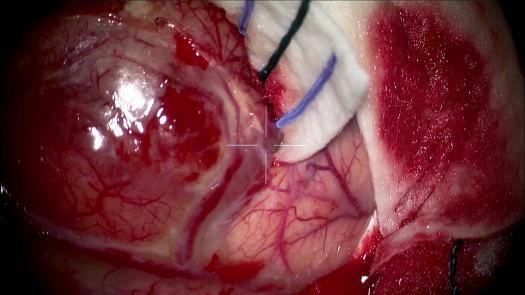

Resezione microchirurgica di tumore cerebrale (glioma alto grado cortico-sottocorticale) frontale dx